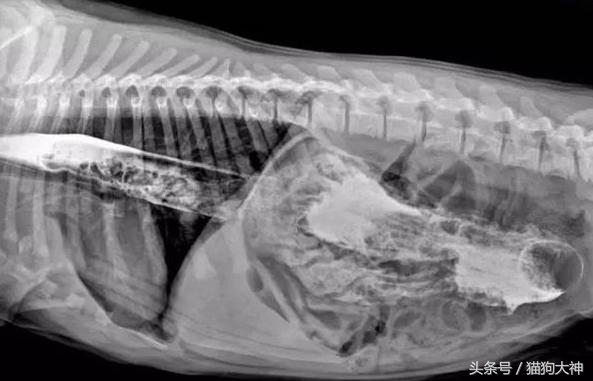

这只大丹犬曾经震惊过整个宠物医疗界。某天,主人发现狗狗精神不振,于是连忙送去了医院。

这是X光片的情况,狗狗的胃里塞满了不知道是什么的东西,反正消化不了并且堵住了肠胃。

手术结束后,医生将从狗狗胃里取出的43只袜子摆在了主人面前,主人简直惊呆,他没想到,家里丢失的那些袜子竟然全部被狗吞了。